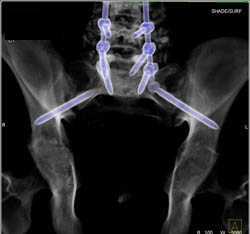

Subtle Talus Fracture